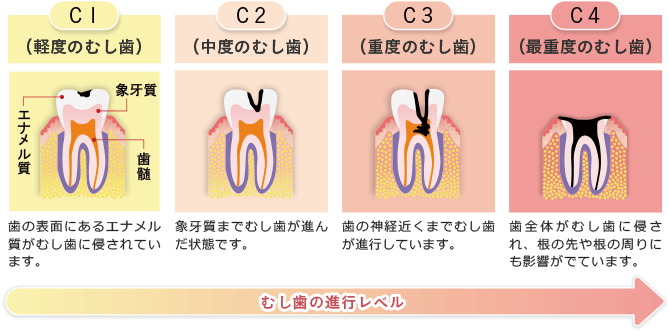

「歯がしみる」「歯が痛い」

そんなむし歯の症状が出てもすぐに受診せず、痛みに耐えられないような状況になってから歯科医院に訪れる方が多くいらっしゃいます。

しかし、むし歯は痛みを感じる頃にはすでに進行していることがほとんどで、ぎりぎりまで痛みを我慢していた場合、治療の時間や費用が多くかかってしまいます。

また、重度まで進行してしまっているむし歯は、神経を抜く必要があったり、場合によっては抜歯が必要になることもあります。

「むし歯かな?」と感じたら、お早めの受診を心がけましょう。

むし歯の進行状況を正確に判断し、丁寧に治療のご説明をしてから治療に入ります。

進行状況に合わせた治療を行うことで、歯の削りすぎを防ぎ、患者様の歯を少しでも多く残せるように心がけています。